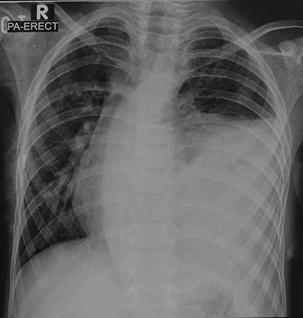

We describe a 6 year old boy with a hybrid lesion consisting of an intralobar pulmonary sequestration associated with a type II Congenital Pulmonary Airway Malformation (CPAM). This is the first case of a hybrid lesion in a child reported in Malaysia. | | | | Case Report | A 6 years old boy presented to our district hospital with chief complains of fever and cough for the past 4-5 days. Child was admitted and treated for an upper respiratory tract infection. However, in view of persistent temperature spikes, a chest x-ray was performed which revealed a left sided pleural effusion (a total whiteout). Child developed intermittent grunting, became increasingly tachypnoeic with suprasternal and subcostal recessions and appeared more lethargic. Trachea appeared to be deviated to the right side, there was dullness on percussion and reduced breath sounds over the left middle and lower zone. Child was intubated and transferred to our Paediatric Intensive Care Unit for further management. On arrival to our center, child appeared to be in a decompensated septic shock requiring inotropic support. An ultrasound thorax done revealed a large heterogeneous highly vascular lesion in the left lower hemithorax with blood supply arising from the abdominal aorta, superolateral to origin of the coeliac artery. A Contrast Enhanced Computerized Tomography (CECT) thorax was done which revealed a heterogeneously enhancing mass seen at the left hemithorax measuring 10.8x11.9x13.1 cm, with numerous fluid-filled cyst within, arterial supply noted to be arising from the abdominal aorta at the level of the coeliac trunk and venous return into the left pulmonary vein. There was a mediastinal shift with a left sided pleural effusion noted as well. A rounded hyper-density was also noted at the lateral aspect of the mass suggestive of an arterial aneurysm. An ultrasound guided biopsy was performed to rule out pleuropulmonary blastoma which revealed no malignant cells. We then proceeded with a thoracotomy. The left lower lobe was filled with pus and adhered to the diaphragm, a feeding vessel was noted from a branch above the coeliac artery piercing through the diaphragmatic tissue. A left lower lobectomy was performed and a chest drain inserted intraoperatively. Post-operative period was complicated with a haemothorax and recurrent pneumonias with parapneumonic effusions requiring prolonged ventilation. Child subsequently recovered and was discharged well. Child has been doing well since then and follow up visits have been uneventful. HPE showed various dilated cystic spaces lined by cuboidal to ciliated pseudostratified columnar epithelium with minimal foci of cartilaginous tissue in intervening area suggestive of CPAM most probably type II with associated inflammatory changes and fibrosis.

Figure 1. Shows erect chest radiograph during his presentation which shows left massive pleural effusion.